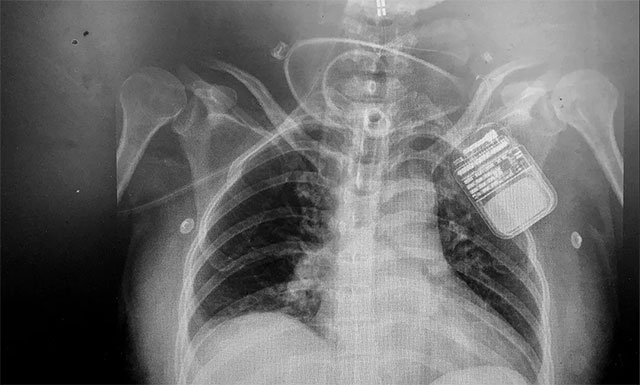

▲ 電刺激器順利置入患者脊髓上方

脊髓神經(jīng)電刺激置入術(shù),是通過微創(chuàng)手術(shù)將電極置入脊髓上方,以脈沖電流刺激脊髓神經(jīng),增加腦血流、腦代謝,而且還能激活腦干網(wǎng)狀上行系統(tǒng),這樣不僅能改善腦循環(huán)、縮小缺血灶,還能興奮大腦皮層,促進患者神志清醒。該技術(shù)具有微創(chuàng)、可逆,并可依據(jù)患者病情需要進行治療參數(shù)的調(diào)節(jié),實現(xiàn)個體化定制,同時可有效改善患者全身循環(huán)水平等優(yōu)勢,對長期昏迷患者有很好的促醒作用。

在對患者進行嚴格的術(shù)前評估后,2020年2月19日,潘仁龍主任領(lǐng)銜的專家團隊對其進行了“脊髓神經(jīng)電刺激置入術(shù)”,手術(shù)順利完成。術(shù)后,根據(jù)張女士的具體病情,對刺激參數(shù)進了調(diào)節(jié),之后她意識情況較前明顯改善,眼睛已經(jīng)可以睜開,眼球可隨人影和聲音移動,四肢肌張力也逐漸恢復正常,僵硬的肢體也變得柔軟,情感反應(yīng)也更加豐富,隨著脊髓神經(jīng)電刺激的持續(xù)調(diào)節(jié)治療,張女士的意識情況將會進一步得到恢復。